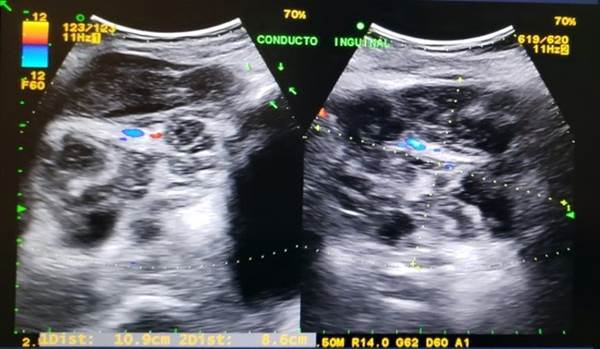

Los estudios de laboratorio preoperatorios mostraron leucocitosis a expensas de neutrófilos, resto de biometría hemática y tiempos de coagulación normales (Tabla 1). La ultrasonografía (USG) de pared abdominal e inguinal mostró presencia de hernia inguinal derecha (Figura 1).